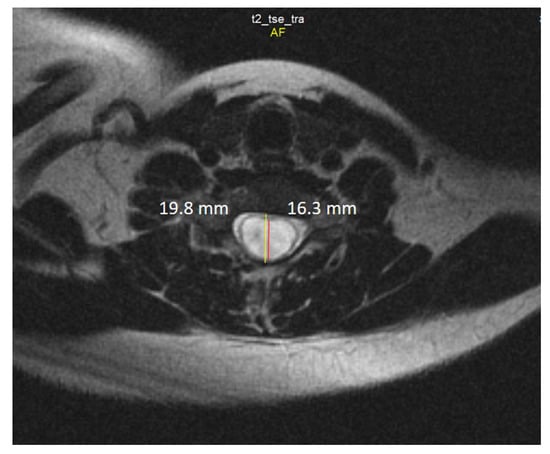

2.4. Neuroimaging

- Klekamp, J. How Should Syringomyelia be Defined and Diagnosed? World Neurosurg. 2018, 111, e729–e745. [Google Scholar] [CrossRef]